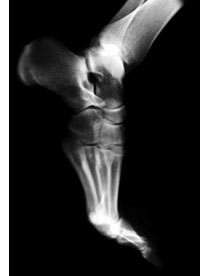

X-Rays

X-rays of the foot or ankle can help us determine whether a bone has

been fractured or injured or damaged by conditions such as an infection,

arthritis, or other disease.